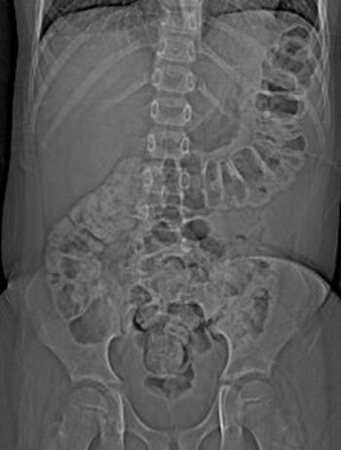

- plain abdominal x-rays:

dilated loops with air-fluid level secondary to ileus; free air is consistent with perforation; in toxic megacolon, the transverse colon is dilated to 6 cm or more in diameter

- abdominal x-ray:

gaseous distension of large bowel; volvulus suggested by kidney-bean-shape bowel loop